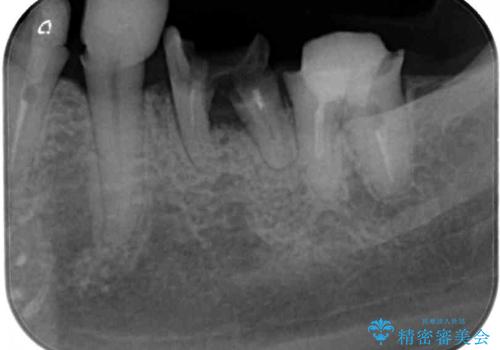

- 虫歯や歯の欠損を放置していることを気にして来院された患者様です。

下顎には抜歯が必要な歯があったため、抜歯後に治癒を待ち、上顎とともにオールセラミックブリッジにて補綴治療を行うこととしました。